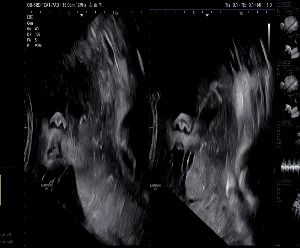

KakaoTalk_20250928_202835448.jpg 자궁경부와 태반까지 3.02cm

34주차 정기검진 날, 이전 정밀 초음파에서 자궁경부와 태반 간 거리가 2.78cm라고 들었고,

화면 속 태반은 여전히 낮은 자리에서 움직이지 않았다.

“부분 전치태반으로 확정해야겠네요.”

선생님은 차분하게 그림 보여주시며 완전 전치태반과 부분 전치태반의 차이를 설명했다.